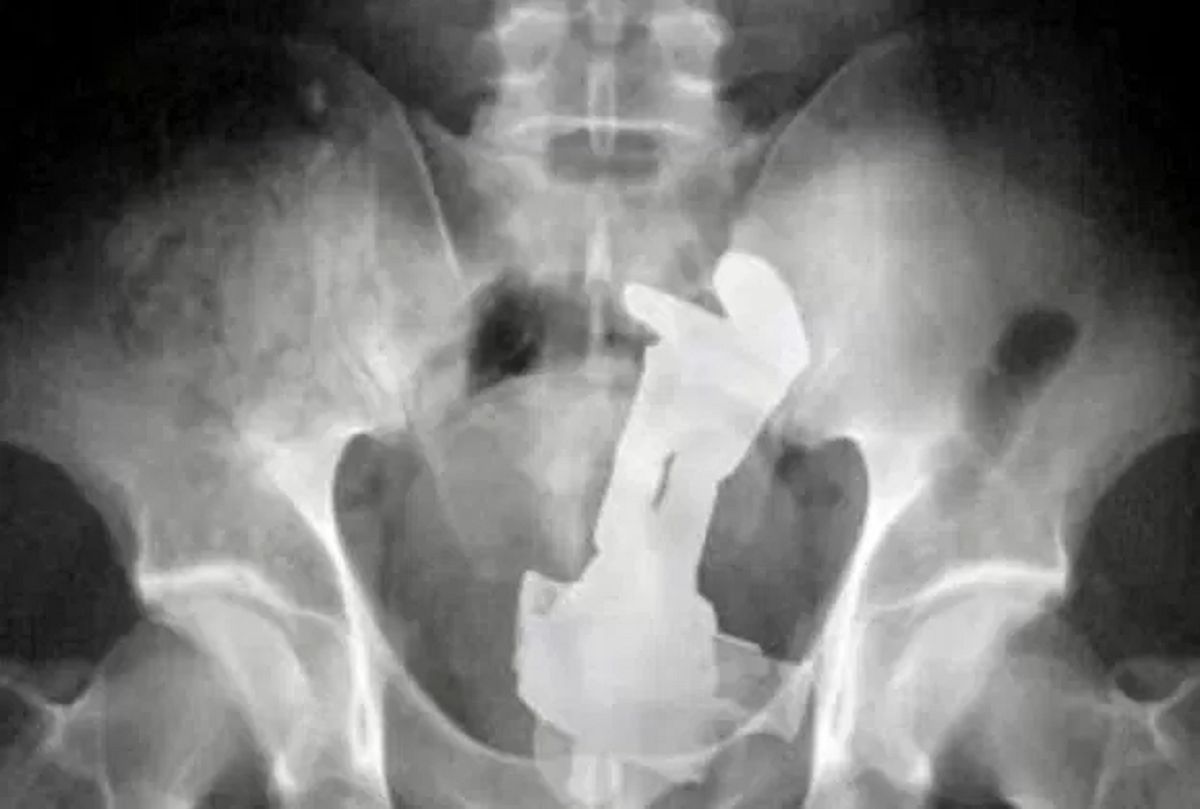

Ponoć ktoś zapomniał się przy zabawie wibracjami...